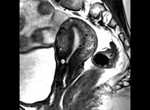

Q116. A woman presents with Chronic lower abdominal Pain and dysmenorrhea. MRI is shown. Diagnosis?

- Adenomyosis

- Endometriosis

- endometrial carcinoma

- Fibroid

Answer: A